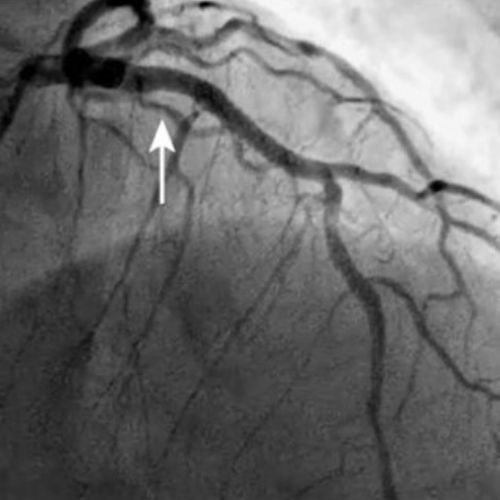

CARDIOLOGIA INTERVENTISTICA CORONARICA

Il Professor Italo Porto ha eseguito più di 4500 angioplastiche coronariche di tutti i gradi di complessità, , ed è particolarmente specializzato nele procedure ad alto rischio (CHIP-complex, high risk, but indicated PCI).

Il Professor Porto utilizza tutte le tecniche più avanzate durante l'angioplastica coronarica, sia di tipo diagnostico (IVUS, OCT, FFR, iFR) che di tipo interventistico (Rotablator, laser, aterectomia rotazionale, litotrissia intravascolare coronarica).